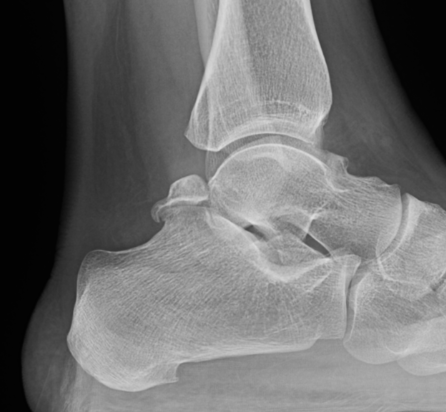

Xray

Os trigonum

Stieda process - elongated lateral process of talus